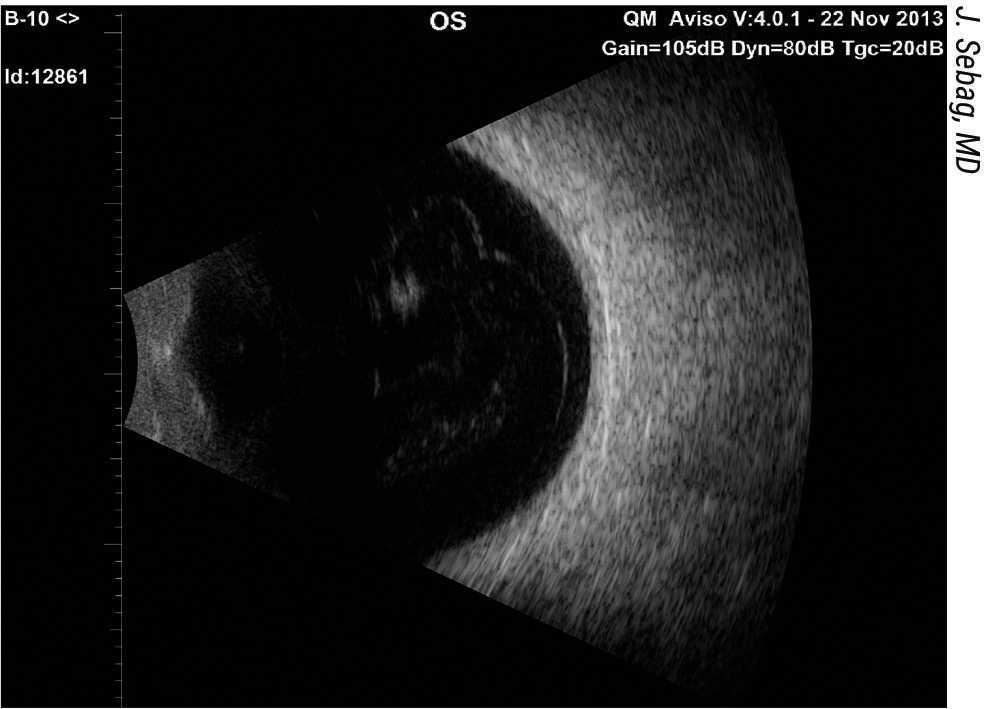

"Me di cuenta de que tenemos que empezar a considerar las moscas volantes como una enfermedad en algunas personas", añade el Dr. Sebag. "Muchas personas tienen moscas volantes sin consecuencias; sin embargo, también hay muchas personas debilitadas por las opacidades que inducen las moscas volantes. Moscas volantes es un término que se utiliza mal; se utiliza erróneamente para referirse a estructuras dentro del ojo, pero las moscas volantes no son estructuras, sino un fenómeno visual creado por opacidades dentro del vítreo. Cuando utilizamos ultrasonidos para obtener imágenes de las estructuras internas del ojo que causan el fenómeno visual de las moscas volantes, empleamos el término 'ecodensidad'", añade.

En colaboración con ingenieros acústicos de Nueva York y el Dr. Alfredo Sadun, del Doheny Eye Institute, de Pasadena, el Dr. Sebag desarrolló unos parámetros que ahora utiliza de forma rutinaria para evaluar a los pacientes que se quejan de moscas volantes. El primer parámetro mide la densidad del vítreo mediante ultrasonido cuantitativo.2 "El ultrasonido solía ser un bastión para evaluar el ojo, pero desde el surgimiento de la tomografía de coherencia óptica la gente tiende usarla en lugar del ultrasonido para obtener imágenes de las estructuras internas del ojo. La OCT es excelente para la retina, pero deficiente para evaluar el vítreo, por lo que el ultrasonido ha llenado ese vacío. Hemos trabajado con ingenieros acústicos para desarrollar modos de cuantificar las imágenes de ultrasonido para evaluar la gravedad de los cambios estructurales dentro del cuerpo vítreo que causan el fenómeno visual de las moscas volantes", añade.

Figura 3. El ultrasonido B-scan demuestra un desprendimiento vítreo posterior y ecodensidades vítreas centrales. Ambos interfieren en la transmisión de fotones a la retina, lo que provoca una degradación de la sensibilidad al contraste debido a la dispersión de la luz.1 La gran ecodensidad de la parte superior de esta imagen podría ser susceptible de vitreolisis con láser YAG, mientras que el resto de densidades y la corteza vítrea posterior probablemente se traten mejor mediante vitrectomía.